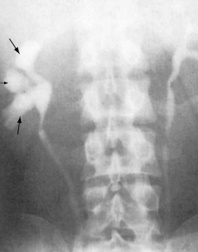

Plain radiography

Plain radiography of the kidney, ureters and bladder (KUB) is a simple, non-invasive test that can be used before specialized imaging. It is used to detect calcification in the kidney, such as renal and urinary tract stones – uric acid stones cannot be detected, but in general 90% of stones are radio-opaque (Figs 8.15 and 8.16). It also shows the size and position of the kidneys (this is unreliable), and any secondary bony deposits (such as can be associated with prostatic cancer).

image

Fig. 8.15 Plain abdominal radiograph showing several calculi in the left kidney (arrows).

(Courtesy of Mr RS Cole.)